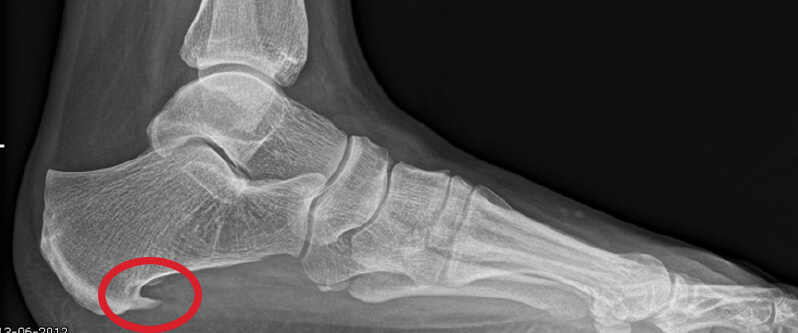

Een hielspoor is een botuitwas (verkalking) aan de onderzijde van het hielbot, het zogenoemde calcaneus. Deze verkalking bevindt zich op de plaats waar de peesplaat onder de voet, de fascia plantaris, aanhecht. Een hielspoor is goed zichtbaar op röntgenfoto’s en kan ook met echografisch onderzoek worden vastgesteld.

Hielspoor duidelijk zichtbaar op deze op röntgenfoto.

Een röntgenfoto kan een hielspoor zichtbaar maken, maar is niet altijd noodzakelijk. Met echografie kan de dikte en kwaliteit van de fascia plantaris worden beoordeeld en kan worden vastgesteld of er sprake is van overbelasting of degeneratie.